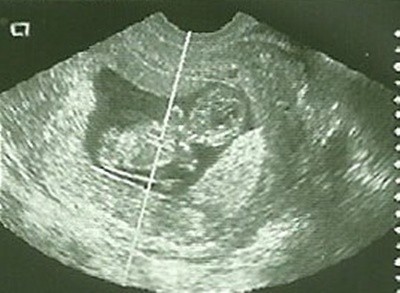

Dziewczyny, naprawdę wielkie dzięki za ciepłe słowa. Nawet nie wyobrażacie sobie, jak strasznie się wczoraj ucieszyłam, widząc nasze rozbrykane dziecię. Po tym jak straciliśmy drugiego aniołka, nie wierzyłam, że w moim brzuszku jeszcze kiedykolwiek ktoś zagości, nie mówiąc o tym, że będzie wyczyniał tam akrobacje! Kiedy gin powiedział, że wszystko jest super i maluch jest zdrowy, po prostu nie mogłam uwierzyć w to, co usłyszałam. Teraz jestem już spokojniejsza i zaczynam powoli bez strachu myśleć o tym, że jestem w ciąży.

Pokażę Wam tego małego urwisa (urwiskę?)- wprawdzie nie dał sobie zdrobić "porządnej" fotki, bo brykał, ale główka wyszła mu cudnie i moje ukochane paluszki u rączek, które mają 2 mm.

1.jpg2.jpg